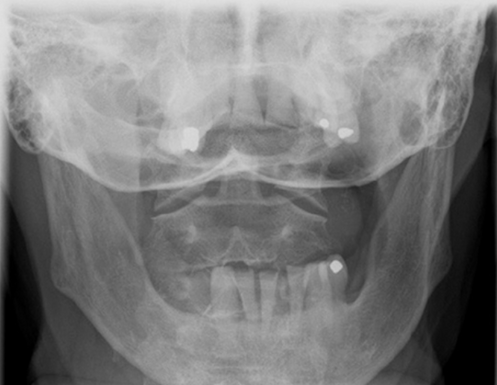

AP Open Mouth: Is this Image Good?

No.

Base of skull superimposed over dens and lateral masses

Atlantoaxial joint is not clearly demoed

Extensive extension of skull

Reposition by slight flexion of the neck or angle the CR slightly caudal

Front incisors are superimposed over C1-C2

Atlantoaxial joint is not demoed

Excessive flexion of skull and neck

Reposition with slight extension of the neck or angle the CR slightly cephalic